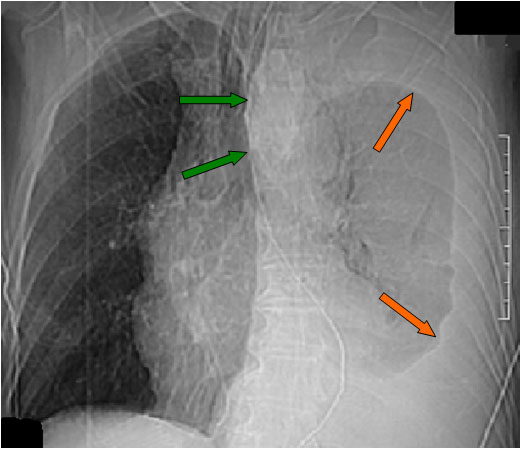

El desplazamiento de la sonda nasogástrica a la derecha (que indica desplazamiento esofágico) en la radiografía de tórax, se ha descrito como el signo más fiable de rotura de la aorta torácica e indica la necesidad de realizar angioTC urgente. La primera imagen muestra el desplazamiento de la sonda (flechas verdes) así como un gran derrame pleural izquierdo (flechas naranjas).